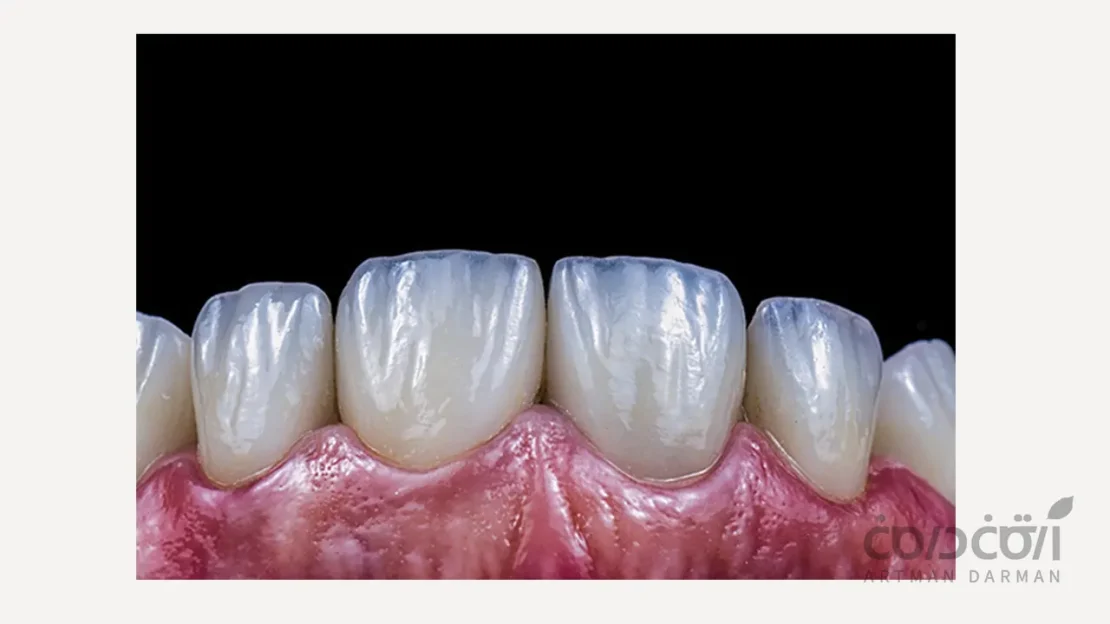

چرا باید نخ دندان استفاده کنیم؟ (+ راهنمای نحوه استفاده از نخ دندان)

برای حفظ سلامت لبخند، توجه به بهداشت دهان و دندان ضروری است.با وجود اینکه مسواک زدن یکی از روش‌های متداول حفظ بهداشت دهان و دندان است، ...